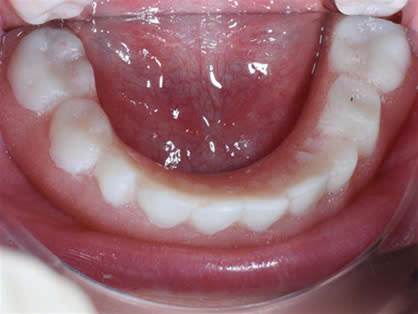

Đặc biệt biểu hiện ở răng:

Tùy mức độ từ nhẹ đến nặng của bệnh mà có biểu hiện ở răng từ thiếu một vài răng đến thiếu nhiều răng đến không có răng.

Trường hợp thiếu răng: răng trong miệng thường bị dị dạng, có dạng hình nón hoặc hình chóp.

Do tình trạng giảm tiết nước bọt trong miệng nên các trường hợp khiếm khuyết men răng và sâu răng xảy ra thường xuyên.

Hình 3: Ảnh chụp trong miệng